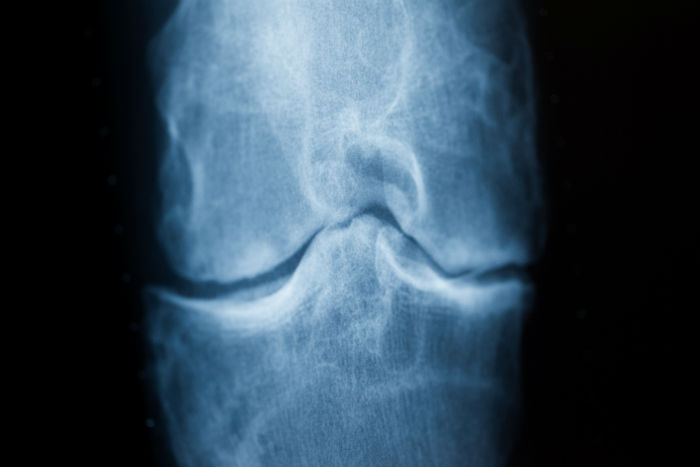

السخونة تخفف آلام التهاب المفاصل

(د ب أ)- قالت الرابطة الألمانية لعلاج الروماتيزم إن السخونة يمكنها تخفيف آلام التهاب المفاصل.

وشددت الرابطة على ضرورة الانتباه لأمرين، أولهما: لا يتم استخدام الماء الساخن أو زجاجة الماء الساخن أو قِربة الماء الساخن على المفصل إلا إذا كان غير ملتهب، وثانيهما: تدفئة العضلات فوق وأسفل المفصل.